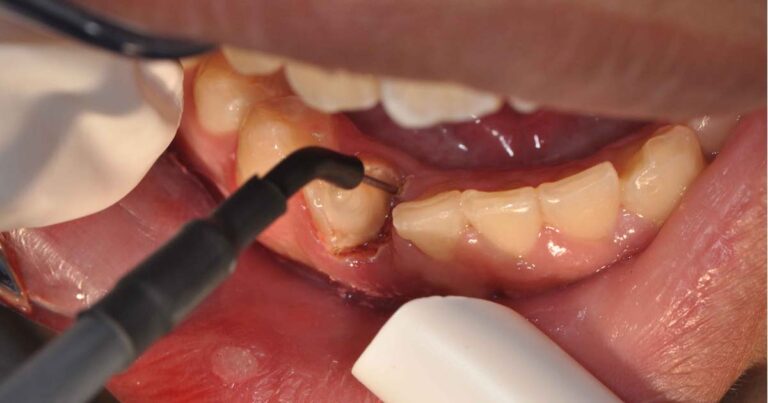

Czym jest elektrokoagulacja? Elektrokoagulacja to zabieg polegający na kontrolowanym wykorzystaniu prądu elektrycznego w celu zamknięcia naczyń krwionośnych oraz usunięcia zmienionych tkanek. W stomatologii metoda ta znajduje zastosowanie przede wszystkim w chirurgii i periodontologii. Stomatolog w nowoczesnej klinika stomatologiczna Kraków wykorzystuje…